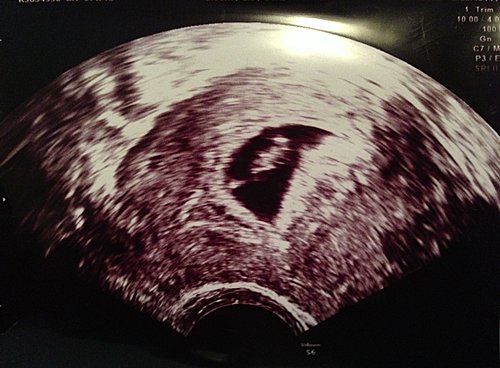

第一次產檢

在去北海道滑雪前才知懷孕,當時約是四個多星期。在日本雖然也百無禁忌地雪照滑,魚生照食。但都事事十分小心。醫生叫回港後去產檢。第一次產檢,是6星期。第一次照超聱波,已經見到胎囊,但胎兒只是小小的一點。雖然只是一點,但已經看到有心跳了,好興奮啦。 醫生亦見,我有3個3CM的纖維瘤,還有個水瘤在左邊卵巢。但醫生說先不要理會這個,胎兒是首要的。醫生也說當胎兒日漸長大,瘤也有機會跟著大,但只會大到某一個程度,不用太擔心。我問她開... 看全文 -